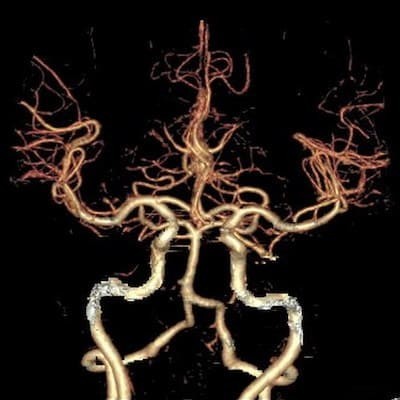

Если говорить о компьютерной томографии сосудов, то визуализация сосудов на КТ требует контрастирования на базе йода. Это обязательное условия, так как без контраста специалисты просто не увидят сосудистое русло.

Преимущество компьютерной томографии сосудов заключается в том, что она хорошо визуализирует аневризмы, и за короткий промежуток времени диагност может просканировать большой участок головной мог и шею, ноги или руки, аорту в брюшном, грудном отделе.

На КТ и МРТ ангиографии будут хорошо отображены даже мелкие артерии и вены. Это более детальная и точная форма диагностики. По своей информативности МРТ и КТ сопоставимы.

Зато КТ ангиография более быстрая форма сканирования. Томография сосудов на ней занимает всего 5-7 минут. МРТ сосудов в ангиорежиме длится около 20 минут.